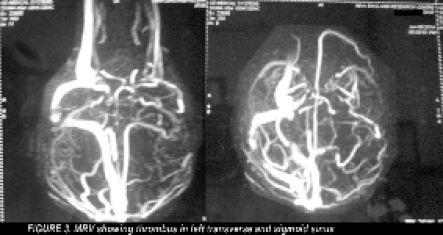

A young unmarried female presented with history of high grade fever of two days duration associated with head ache, vomiting, reeling sensation followed by delirium and seizures after roaming in a very hot summer day. Before getting admitted in the hospital she was treated with cold and wet blankets, intravenous fluids and antipyretics for one day . There was no history of any significant illness. She was not on any medication. On examination, patient was afebrile, drowsy and incoherent. Headache and vomiting are present. There were no signs of meningeal irritation or focal neurological deficits. Papilloedema was present. Her blood sugar, renal and liver function tests and electrolytes were within normal limits. Pregnancy test was negative and urine examination was normal. Computerised Tomogram of brain [Figure: 1] revealed hemorrhage in left temporal region associated with edema. Magnetic resonance scan of brain [Figure:2&3] showed hemorrhagic infarct in the left temporal region and thrombus in the left transverse and sigmoid sinus. Her connective tissue profile was normal (Antiphospholipid antibodies, Antinuclear antibodies, Anti ds-DNA were negative and, Protein C, Protein S, AntiThrombin III and Homocysteine were within normal limits).

- MRV showing thrombus in the left transverse and sigmoid sinus.